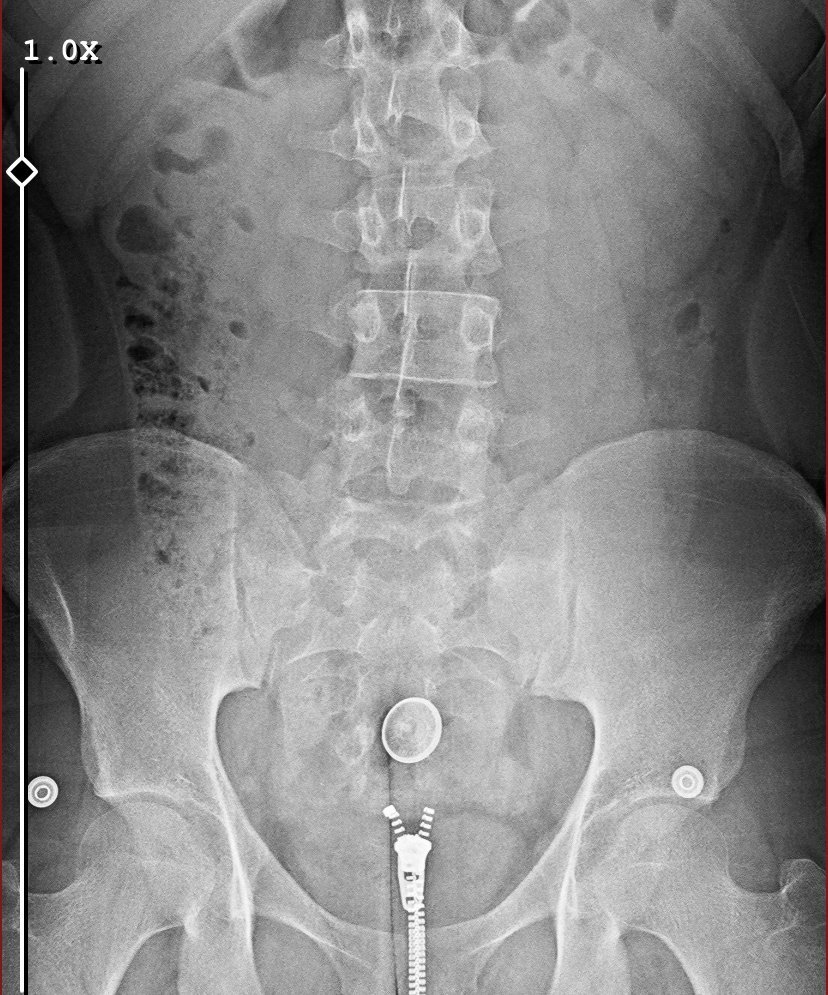

epifiz plağımın kapanıp kapanmadığı buradan anlaşılır mı